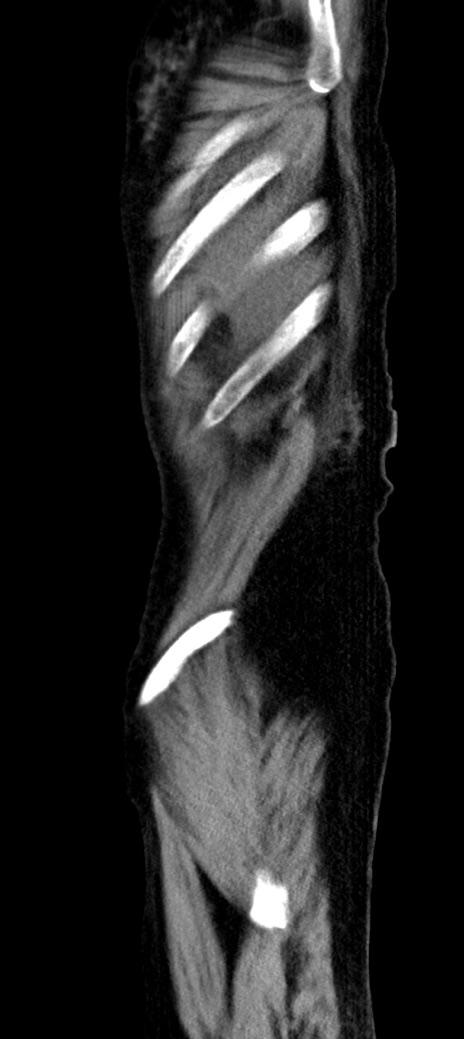

横断像

冠状断像

他院CT